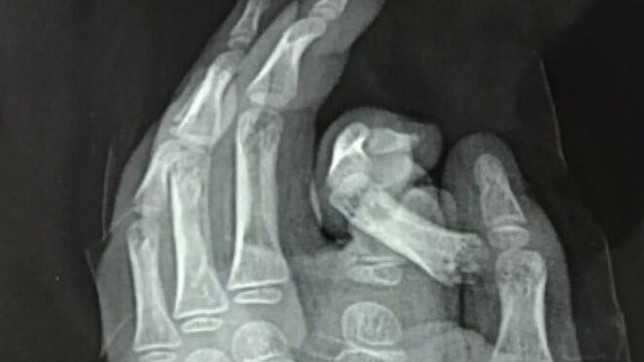

Đút tay vào máy giặt, bé trai đứt ngón trỏ

Hướng dẫn nuôi dạy con -  20/12/2020

Bé được đưa vào cấp cứu tại Bệnh viện Đa khoa Xanh Pôn, ngày 17/12. Các bác sĩ đã cố gắng bảo tồn và nối ngón tay cho bé. Tuy nhiên, tình trạng dập ná...